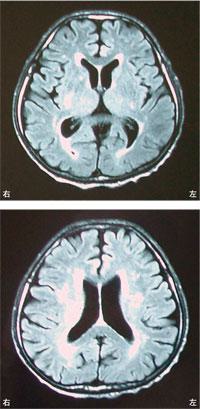

7

理学療法士実地問題 -

第46回 午前

重要度:最重要

75歳の男性。高血圧と糖尿病の治療を長期にわたり行っている。徐々に歩行障害がみられるようになり、転倒することが多くなった。頭部MRIを示す。画像所見で考えられるのはどれか。

1

視床出血

2

硬膜下出血

3

くも膜下出血

4

正常圧水頭症

5

多発性脳梗塞

8

75歳の男性。高血圧と糖尿病の治療を長期にわたり行っている。徐々に歩行障害がみられるようになり、転倒することが多くなった。頭部MRIを示す。この患者で認められないと考えられるのはどれか。

嚥下障害

感情失禁

小刻み歩行

認知機能低下

左側弛緩性麻痺